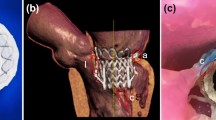

Mitral valve regurgitation (MR) is one of the most common heart disorders and its prevalence increases with patient age.10 Although a surgical repair or replacement of the mitral valve is a primary treatment for symptomatic severe MR, for the very elderly patients or those with significant comorbidities, the risk of surgical valve intervention is too great. Increasingly, catheter-based repair of the mitral valve is being considered for such patients. Today the catheter-based repair of MR is limited to: (1) the use of the MitraClip system to create a fixed coaptation of the two mitral leaflets (Abbott Vascular, Abbott Park, IL);4 (2) the use of a vascular closure devices to occlude a mitral leaflet perforation;3,5 and (3) early trials and ongoing development of trans-catheter mitral valve replacement (TMVR) devices.4 The typical procedural stages of a MitraClip deployment are shown in Fig. 1. A principal limitation of each of the trans-catheter mitral treatments is our current inability to accurately predict how the repair or replacement device will interact with complex native and pathologic geometry of the patient, and how well the device will achieve the treatment goal—namely the elimination or significant reduction of MR.

Catheter-based mitral valve repair. (a) 3D TEE image of regurgitant mitral valve (MV) prior to MitraClip procedure. (b) 3D TEE image of the MitraClip deployment during the percutaneous MV repair. (c) 3D TEE image of repaired MV with implanted MitraClip device; anterior leaflet (AL), posterior leaflet (PL).